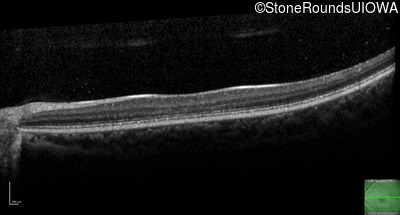

AR Stargardt Disease (IIA)

Age at visit:

15 years

OD

OS

20/125 -1

20/80

AR Stargardt Disease

ABCA4

Val256Val GTG>GTT

Gly1961Glu GGA>GAA

AR